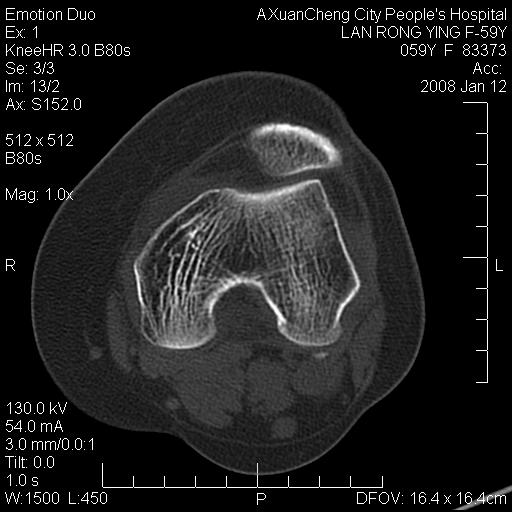

标题: CT11294:股骨内侧髁病变 [打印本页]

标题: CT11294:股骨内侧髁病变

左膝关节痛3月

支持骨岛(长椭圆形+长轴与骨小梁一致+边界清楚)。

考虑为股骨内侧髁致密骨岛。

致密性骨岛?不知软组织是否为正常的肌肉,如果病人软组织肿胀并见肿物,那成骨转移不能除外,毕竟是高危年龄阶段。